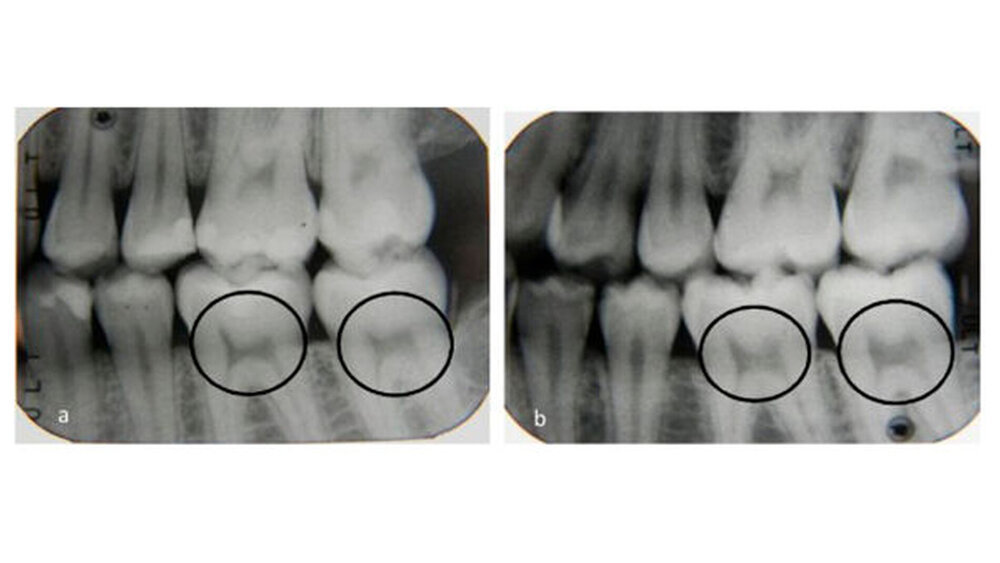

Die Form der Pulpa im gesunden Zahn ähnelt bekanntlich einem Bogen, der von zwei Katzenohren gekrönt wird, während sie bei Personen mit schwerem Vitamin D-Mangel asymmetrisch und verengt ist und typischerweise wie ein Stuhl mit harter Lehne aussieht.

Den Autoren zufolge gehen Vitamin-D-, Calcium- oder Phosphat-Mängel mit Veränderungen der Pulpenkammern aufgrund der abnormalen Mineralisierungen einher. Zellstoffanomalien könnten daher die erste Evidenzstufe für einen zuvor nicht diagnostizierten Vitamin D-Mangel sein.